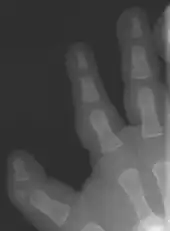

Triphalangeal thumb

Triphalangeal thumb (TPT) is a congenital malformation where the thumb has three phalanges instead of two. The extra phalangeal bone can vary in size from that of a small pebble to a size comparable to the phalanges in non-thumb digits. The true incidence of the condition is unknown, but is estimated at 1:25,000 live births.[1] In about two-thirds of the patients with triphalangeal thumbs, there is a hereditary component.[2] Besides the three phalanges, there can also be other malformations. It was first described by Columbi in 1559.[3]

The triphalangeal thumb has a different appearance than normal thumbs. The appearance can differ widely; the thumb can be a longer thumb, it can be deviated in the radio-ulnar plane (clinodactyly), or thumb strength can be diminished. In the case of a five-fingered hand it has a finger-like appearance, with the position in the plane of the four fingers, thenar muscle deficiency, and additional length. There is often a combination with radial polydactyly.